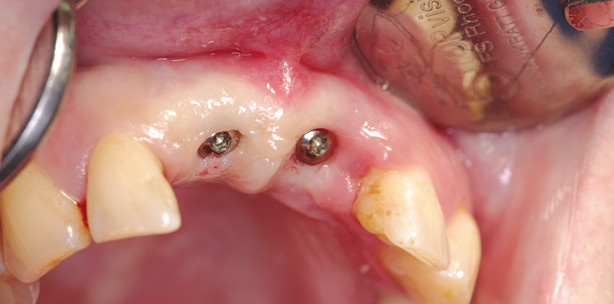

Die Patienten (Mitte 30) hatte schon mehrere Zähne im Seitenzahngebiet des Oberkiefers verloren, wobei ihr ausgeprägter Nikotinabusus mit an Sicherheit grenzender Wahrscheinlichkeit kein unbedeutender Co-Faktor dieses unerfreulichen Geschehens war. Ein vor vielen Jahren erlittenes Frontzahntrauma (häuslicher Sturz) bedingte damals die Schienung der beiden oberen mittleren Schneidezähne, die nun ein knappes Jahrzehnt später hohe Lockerungsgrade aufwiesen. Ferner lag ein ausgeprägter Schmerz beim Abbeißen vor. Nach vorgängig erfolgter Herstellung einer klammerlosen Interimsteilprothese erfolgte die unter maximaler Vermeidung trau­matisierender Momente durchgeführte Entfernung der ­beiden oberen mittleren Inzisivi. Auch hier kam die Kol­lagenmembran- und -kegeleinheit zum Einsatz; beide ­Alveolen wurden entsprechend versorgt. Gerade angesichts des Nikotinabusus, den abzustellen die Patientin nicht bereit war, war ein Struktur- und Volumenerhalt ebenso bedeutsam wie die Erzielung eines möglichst ­raschen und möglichst dichten Verschlusses durch die Kollagenmembran- und -kegeleinheit. Nach vier Wochen primärer Abheilzeit wurden zwei Implantate Regiones 11, 21 inseriert, die nach weiteren acht Wochen mit zwei ­Kronen als Suprakonstruktion versorgt wurden.